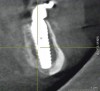

When such instances occur, whether in the mandible or maxilla, the author first attempts to place a larger-diameter implant of the same length as the implant that failed to achieve high initial torque value. Should this adjustment prove ineffective, a longer implant of a larger diameter is then used. In the maxilla, the longer implant may engage the vomer or lateral piriform rims to achieve apical stability.13 In the mandible, the author achieves primary implant stability by engaging the cortical bone at the inferior border of the mandible with the apical portion of the dental implant (Figure 14 and Figure 15).

Fig 14. Postsurgical panoramic radiograph of All-on-4–style dental implant surgery with dental implants engaging cortical bone at the inferior border of the mandible.

Figure 14

Fig 15. Cross-sectional CBCT scan slice from Figure 14 showing apical engagement of the dental implant with the dense cortical bone at the inferior border of the mandible.

Figure 15